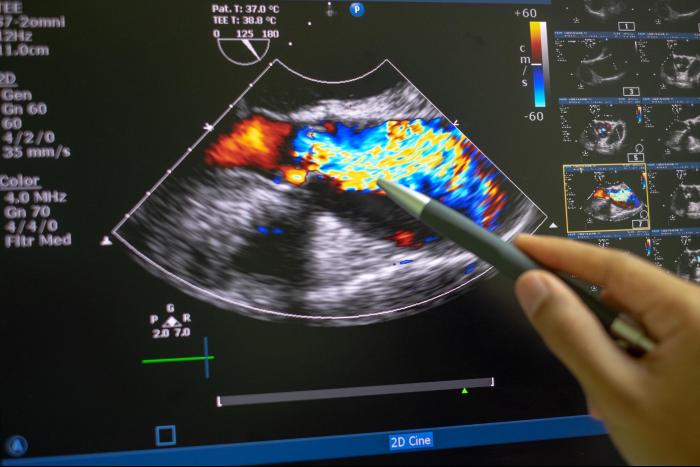

¿Te gustaría dar un paso adelante en tu camino profesional? Pues esta información es para ti. Emagister te presenta el programa de Experto en Ecografía Doppler que lo desarrolla e imparte Editorial Médica Internacional Ltda en su modalidad virtual durante 6 meses.

El especialista que realice este curso será capaz de realizar exploraciones mediante ecografía Doppler de forma sistematizada en todas las áreas del cuerpo humano.

Profundizarás en temas como Bases de la ecografía Doppler, Ecografía Doppler de la cabeza, cuello y extremidades superiores , Ecografía Doppler de las extremidades inferiores, Ecografía Doppler del abdomen y la pelvis, Ecografía Doppler en situaciones especiales, entre otros.